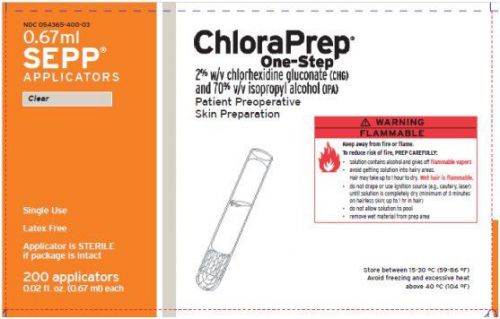

ChloraPrep One-Step. SEPP Applicators (box of 200)